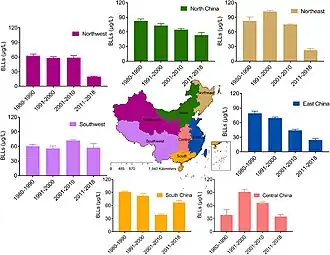

Map showing the mean blood lead levels (BLLs) of adults in China during 1980–2018.

Map showing the mean blood lead levels (BLLs) of adults in China during 1980–2018. Trend of blood lead levels (BLLs) in Chinese adults in different regions from 1980 to 2018. A decreasing trend was found in all regions except for South China.[252]

Trend of blood lead levels (BLLs) in Chinese adults in different regions from 1980 to 2018. A decreasing trend was found in all regions except for South China.[252]